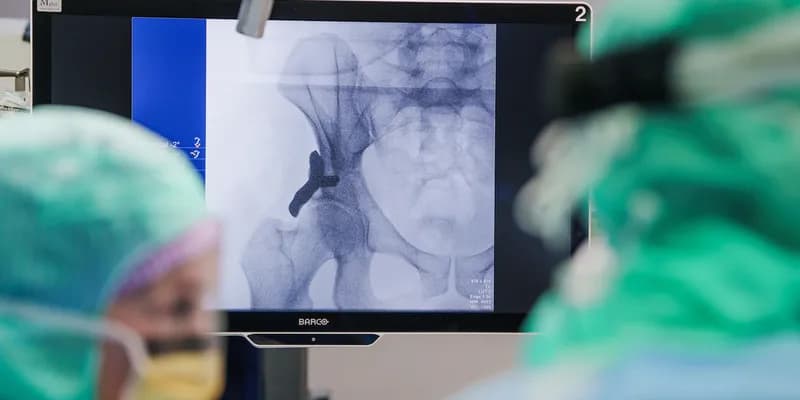

El Hospital Anna, ubicado en Geldrop (Noord-Brabant), ha realizado con éxito la primera operación en humanos utilizando un implante de cadera impreso en 3D.

El procedimiento se llevó a cabo a un paciente de 36 años que sufre de displasia de cadera, una condición en la que la cavidad de la articulación está mal formada, causando dolor y movilidad limitada.

El implante fue diseñado específicamente para adaptarse a la anatomía única del paciente y busca mejorar la estabilidad de la articulación, reducir el dolor y acelerar la recuperación en comparación con los métodos quirúrgicos tradicionales.

Según el hospital, la cirugía se desarrolló sin complicaciones.